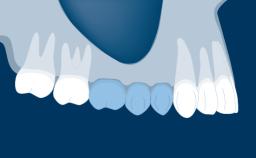

Fixed and removable prosthodontic implant therapy for restoration of the edentulous maxilla is both complex and challenging. Careful assessment and planning is needed in each individual case to explore whether a fixed or a removable solution will be the more suitable to satisfy the patient’s preference for optimal esthetics, phonetics, comfort and function. This Learning Pathway explores the prosthodontically driven treatment planning based on structured assessment, considered diagnosis and practical application in clinical case examples.

• recognize the importance of a prosthodontically driven plan and of planning implant configurations and placement accordingly

Edentulous Maxilla Fixed vs. Removable Prosthodontics Planning Principles Prosthodontic Planning & Procedures Prosthodontic Planning & Procedures